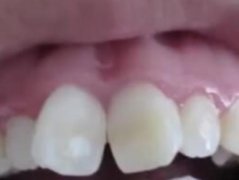

我小時(shí)候我們家,經(jīng)濟(jì)條件并不是很好,較常見的零食就糖,所以我經(jīng)常吃糖。當(dāng)時(shí)我的牙齒就已經(jīng)有稀疏的癥狀了,但是因?yàn)榧依餂]錢,所以就沒有帶我去醫(yī)院看。一開始小的時(shí)候還沒有覺得我的牙齒什么的,但是長(zhǎng)大之后出去上學(xué),總是因?yàn)槲业难例X感到自卑。所以我就想做牙齒矯正,但是聽別人說(shuō)牙齒矯正需要帶牙套,我但心帶牙套影響形象,所以很猶豫。我的朋友推薦我去做隱形牙套矯正,那就跟大家分享下我的經(jīng)歷。